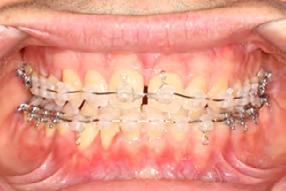

4). Archwires were upgraded incrementally into 19 x 25 SS. Once the bite was completely closed, the patient was referred to the myofunctional therapist to begin treatment. Eight sessions of myofunctional exercises were performed, focusing on muscle building, toning, synchronicity and awareness. Improvement in correct chewing, swallowing and resting postures of the lip and tongue were addressed. All appliances were removed 21 months after initial insertion (Figure 5), and the patient was referred to a re-

storative dentist for veneers on the maxillary central incisors; the patient opted for gold veneers (Figure 6). Clear removable retainers were inserted with a fixed mandibular retainer canine-to-canine.

Treatment Results

The patient finished with Class I occlusion, ideal overbite and overjet. The arches are co-

Figure 5. Final records.

ordinated, lateral open bite closed and occlusal cants leveled. From the frontal cephalometric tracings, maxillary width increased from 58 mm to 69 mm. From the lateral cephalometric tracing, the incisor angulations remained unchanged. The final report from the myofunctional therapist indicated the patient eliminated the bilateral posterior tongue-thrust swallowing pattern with saliva, liquid and solid swallows. Correct swallowing mechanics were demonstrated while sipping/gulping liquids from a cup. His day and nighttime tongue-resting postures were reported to be on his incisive papilla, with lateral margins lightly suctioned into the upper arch. Lips were closed and competent diurnally and nocturnally.

Most recent records are two years after removal of the orthodontic appliances, demonstrating the stability of the results (Figure 7).